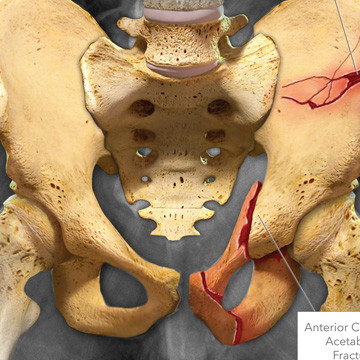

Illustrated X-ray showing severe fractures of the pelvis